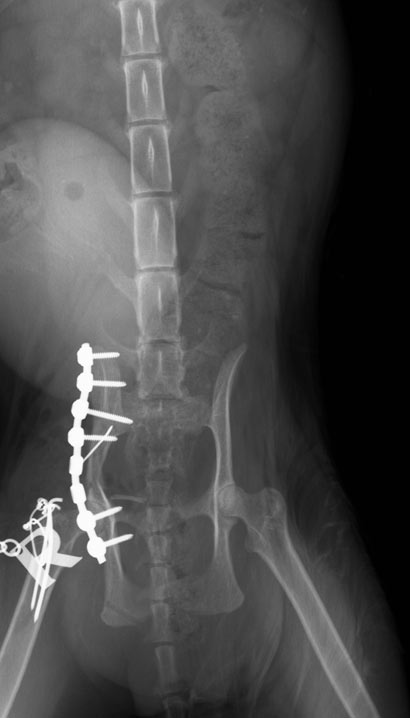

Ihr Becken war verschoben und sie konnte mit der rechte hinteren Pfote nicht auftreten (siehe Video).

Noch am gleichen Tag ließen wir die arme Maus in die chirurgische Klinik bringen, wo sie sofort aufgenommen und geröngt wurde. Mit diesen Verletztungen musste sie sehr, sehr große Schmerzen haben.

Da die Frakturen schon mehrere Tage alt waren, musste Lucky schnellstmöglich operiert und ihr Becken mit Platten und Schrauben wieder fixiert werden.